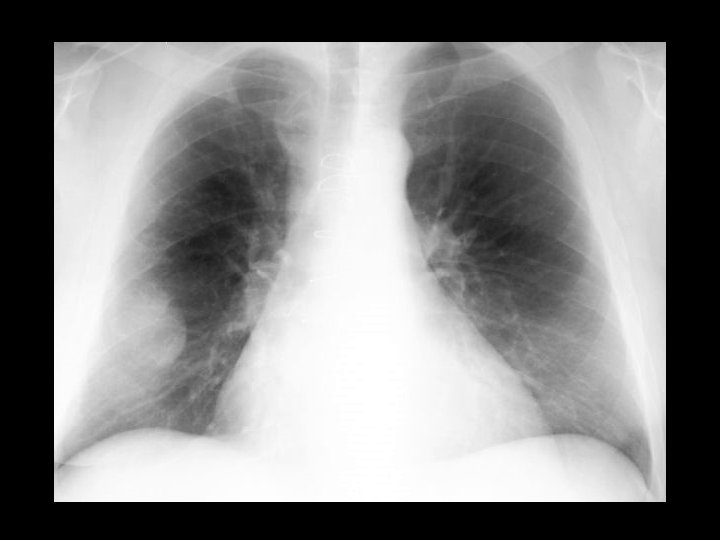

Congenital Reubella w/patent ductus arteriosis • • • Findings: – cardiomegaly, enlarged pulm arteries – longitudinal striations of sclerotic and radiolucent areas at the metaphyses (“celery stalk” appearance) – epiphyseal center not seen – dense, irregular metaphyseal bands most common viral infxn w/bone changes (also CMV) IUGR, TTP, cataracts, sensorineural hearing loss, PDA, pulm art and Ao stenoses